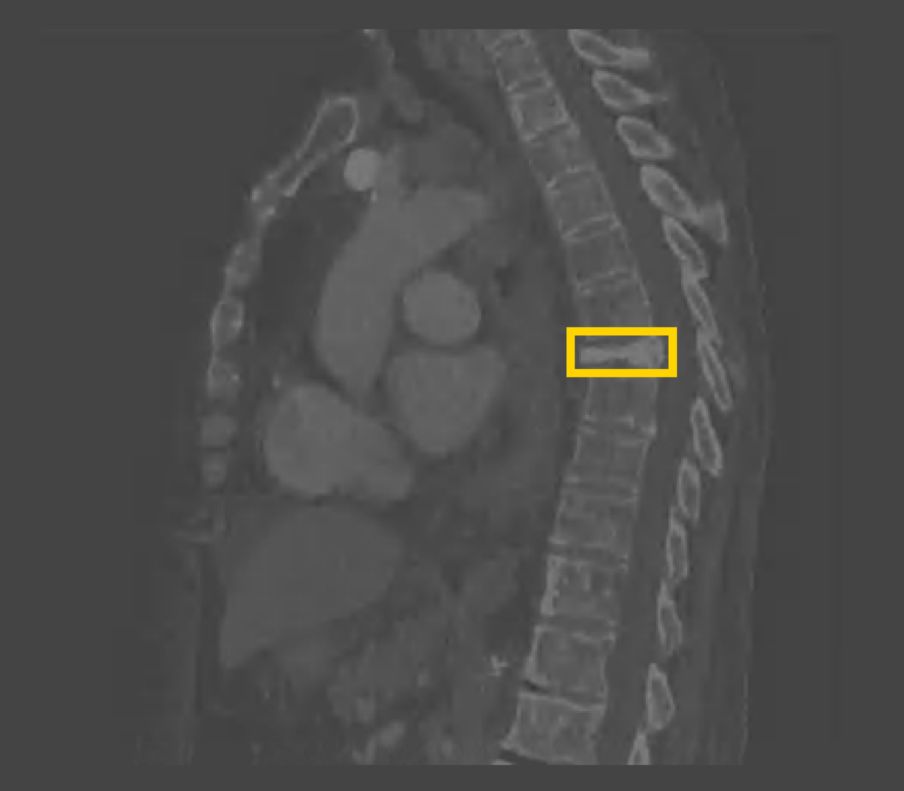

(Zebra Medical Vision:骨骼诊断产品)